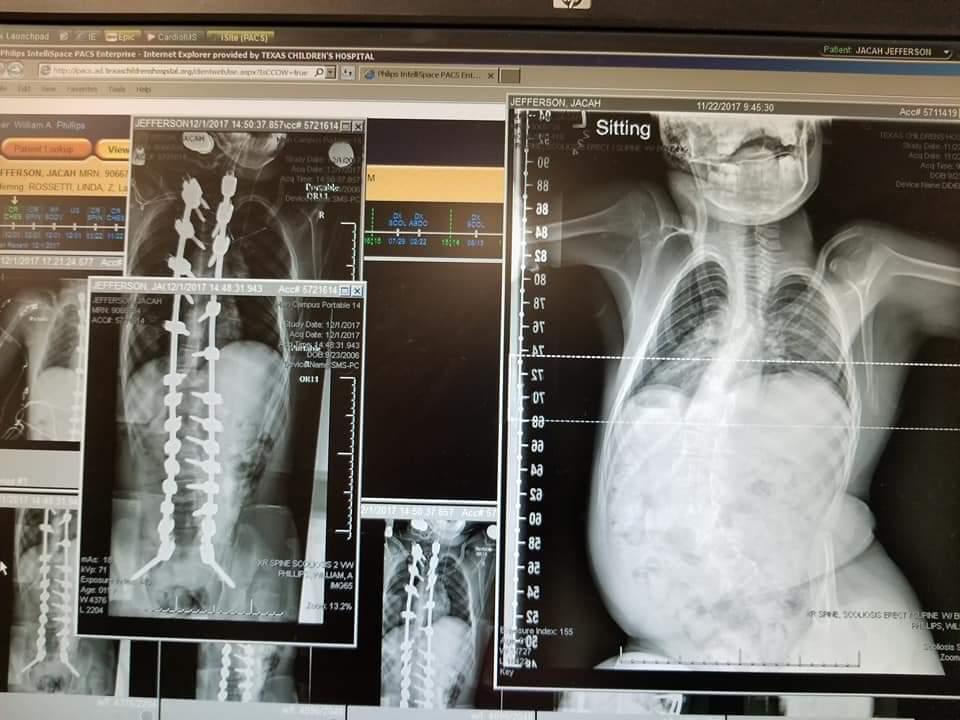

On September 23, 2006 a healthy 6lb 2oz, 19 inch baby boy blessed this earth with his presence. His name is Jacah J’Don Jefferson. After 5 short months of life (March 2, 2007) Jacah was brutally beaten/abused by his biological mother’s boyfriend. His lifeless body was taken to Memorial Herman Northwest reporting trouble breathing. He was then immediately transferred to Texas Children’s Hospitial where they discovered 4 fractured ribs that were healing, a fractured right leg that was healing, an upper jaw fracture, inner nose bone fracture, blood behind both eyes, brain bleeds, and possible seizures. Doctors diagnosed him with Shaken Baby Syndrome also called Abusive Head Trauma which means a serious brain injury resulting from forcefully shaking an infant or toddler. His injuries were so severe that doctors believed he would be blind, need a trachea, and may not even survive. After being discharged to a relative that gave him back to CPS, 2 foster homes that he endured more abuse, God saw fit to bless his maternal grandparents with custody on July 14, 2007! This responsibility among other things lead to a split in the grandparents marriage and after 2 years his entire biological family faded away. Jacah continued to reside with his step-grandmother (Stacy Williams); whom he calls “Mama”, the only dad he knows; Dexter, and his uncles Jeffery and Ernest. As a result of the abuse; Jacah suffers from Cerebral Palsy, Seizure Disorder, Developmental Delays, and Visual impairments. In December 2017, Jacah underwent his 1st surgery to correct his scoliosis. With all that he endures, Jacah lives his “Life After Shaken Baby Syndrome” to the fullest. He is a lover of music, traveling (especially by cruise ship), and continues to be the center of attention to his family. Jacah is known for his million dollar smile and wardrobe (especially his tennis shoes). In 2015 Jacah won the hearts of many across the nation with his #TeamJacah movement in a quest to purchase a wheelchair accessible van. He is the inspiration of the nonprofit organization “Love Has No Disability Inc.”